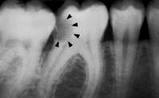

La información

radiográfica contribuye significativamente a los hallazgos

clínicos en términos del hallazgo de lesiones en diferentes

estadíos de progresión (29,32)

Las radiografías ayudan a estimar la profundidad de

desmineralización por caries en el esmalte y la dentina. La

profundidad no siempre está asociada con la presencia de

cavidad de caries, en especial en superficies proximales.

Investigaciones

clínicas que se realizaron en un país con una tasa baja de

progresión de caries revelaron que, en promedio, el 32% de

las lesiones visibles radiográficamente que se extendían

hasta el tercio externo de la dentina no había cavidad de

caries; por el contario, el 72% de las lesiones que se

extendían hasta 2/3 partes de la dentina tenían cavidad de

caries (33) Las

lesiones con cavidad de caries clínicamente o las lesiones

con obvia radiolucidez en dentina (más profunda que el 1/3

externo) en la superficie oclusal están altamente infectada

la dentina, debajo de la unión amelo-dentinaria (34,35)

Sistema radiográfico ICDAS

(Radiografía Bite-Wing) |

R0 |

No hay

radiolucidez |

RA1 |

Radiolucidez en

1/2 externa del esmalte |

RA2 |

Radiolucidez

en la 1/2 interna del esmalte ± UAD

(Unión amelo-dentinaria) |

RA3 |

Radiolucidez

limitada al 1/3 externo de la

dentina |

RB4 |

Radiolucidez que

alcanza hasta el 1/3 medio de la

dentina |

RC5 |

Radiolucidez que

alcanza hasta el 1/3 interno de la

dentina, clínicamente cavitada

RC6 |

Radiolucidez en

la pulpa, clínicamente cavitada

Tabla 4: Clasificación

radiográfica ICDAS